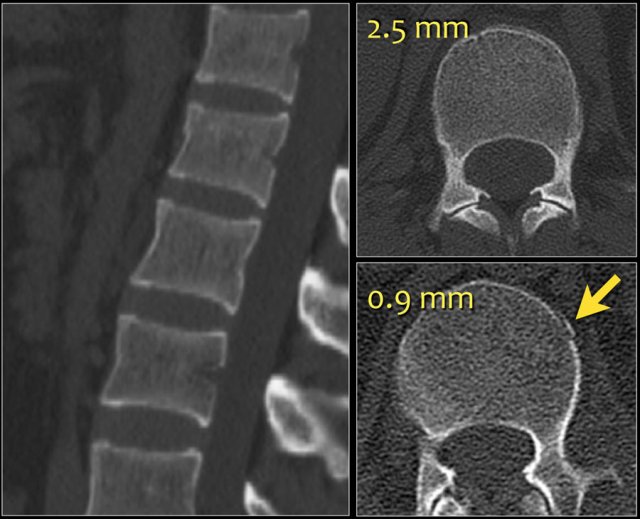

The images show a compression fracture.

All we see is a cortical disruption in the upper anterior wall of the vertebral body and slight loss of height ventrally.

The posterior vertebral cortex is intact.

The sagittal reformatted image also shows the cortical disruption.

Notice that on a 2.5mm axial slice you can miss these fractures.

You have to look at the thin slices to detect such a subtle fracture.

Scroll through the images.

Notice the horizontal band of density, which is often described as sclerosis.

This density does not mean that it involves an older fracture that is already healing with sclerosis.

This is merely a sign of trabecular impaction in an acute fracture.

It is very common to see more fractures on imaging with CT and MRI than on the radiographs.

In this case the CT shows 2 fractures and the MRI shows 3 fractures.